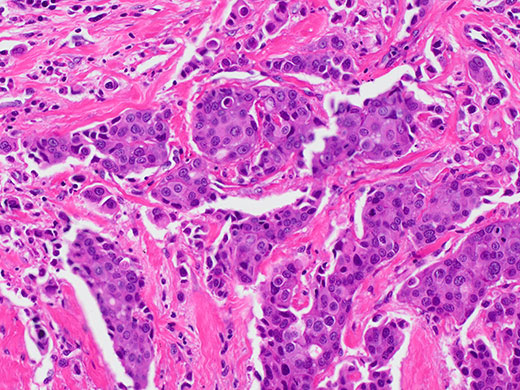

兼具强悍功能、精准的色彩精确度以及宽视场4K分辨率的DP28数码显微相机能够为会议、教学和临床研究提供出色的图像。具备智能功能的相机在提供高质量图像的同时还可简化和加快您的显微镜检查任务。

DP28相机能够在显示器上获得良好的色彩还原和色彩平衡。

- 专用ICC配置文件能够以自然色彩显示样品

- 让常见的生命科学染料看起来与预期别无二致

- 将相机与奥林巴斯TruColor LED和BX53显微镜配合使用即可获得色彩优化显微成像系统